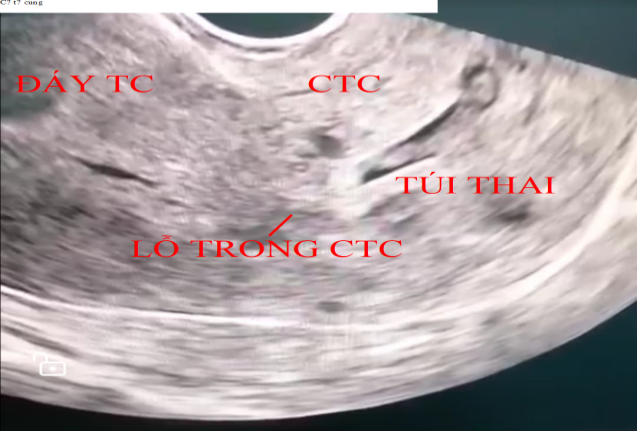

Hình 1. Hình ảnh siêu âm đầu dò âm đạo túi thai làm tổ tại cổ tử cung; cổ tử cung phình to; dòng máu xung quanh nguyên bào nuôi thấy trên phổ Doppler

Bệnh nhân L.T.N.H 42 tuổi, PARA (2092) 2 lần sinh thường, 9 lần sẩy thai có nhiều lần can thiệp buồng tử cung, trể kinh, thử thai dương tính đi khám tại phòng khám tư nhân với chẩn đoán thai làm tổ ống cổ tử cung, bệnh nhân được nhập viện cùng ngày, lâm sàng trể kinh 2 tuần, không đau bụng, không ra máu âm đạo, đặt mỏ vịt thấy cổ tử cung lớn, mạch máu tăng sinh nhiều, nổi rõ mạch lên tại vùng cổ tử cung, cổ tử cung hở lỗ ngoài, siêu âm thai 6 tuần tại vị trí cổ tử cung, tim thai dương tính, phổ Doppler thấy tăng sinh mạch mạnh tại vùng cổ tử cung và có tính hiệu Doppler màu tại bánh nhau.Bệnh nhân được làm xét nghiệm công thức máu, chức năng gan, thận và chức năng đông máu trong giới hạn bình thường. Bệnh nhân theo dõi tại viện sau 3 ngày (vào viện chiều thứ 6) và hội chẩn khoa tại phòng siêu âm: chẩn đoán thai 6 tuần 3 ngày làm tổ tại cổ tử cung, tim thai dương tính. Xét nghiệm beta hCG 78352 mIU/ml, được chỉ định điều trị tiêm MXT tại chổ và hóa trị liệu toàn thân bằng MTX: Tiến hành hút hết ối, tiêm MTX tại khối thai 25 mg, tại bánh nhau 25 mg, sau 2 tiếng kiểm tra tim thai âm tính tiêm bắp MTX25 mg (tổng liều 75mg). Sau 3 ngày bệnh nhân xuất hiện đau bụng vùng dưới, tiến hành nạo gắp khối thai chủ động bằng kẹp đầu vợt, máu tại cổ tử cung ra nhiều, dùng sonde foley số 16 bơm từ từ lên 50 ml nước thì cầm được máu, lưu sonde, theo dõisau 20 phút bóng tuột, tiến hành đặt lại bóng với 50 ml nước muối, sau đó chèn gạc kín âm đạo, sau 24 giờ rút sonde, không còn ra máu. Kết quả xét nghiệm lại β-hCG 4626 mIU/ml. Bệnh nhân được cho ra viện sau đó 2 ngày. Sau một tuần xét nghiệm β-hCG 343.18 mIU/ml, sau 5 tuần β-hCG 2.42 mIU/ml. siêu âm tử cung phần phụ chưa phát hiện bất thường.

Triệu chứng phổ biến nhất là chảy máu âm đạo sau một thời gian vô kinh, thường không đau và đôi khi chảy máu ồ ạt. Tiêu chuẩn lâm sàng bao gồm [4]: Tử cung nhỏ, cổ tử cung phình to; Lỗ trong cổ tử cung kín; Nạo niêm mạc tử cung không có mô nhau; Lỗ ngoài cổ tử cung mở to hơn sẩy thai.Mang thai OCTC sớm cũng có thể không có triệu chứng và được phát hiện tình cờ trên siêu âm.Siêu âm qua ngã âm đạo có thể được thực hiện một cách an toàn ở những bệnh nhân thai OCTC và việc chẩn đoán chủ yếu dựa vào kết quả siêu âm. Theo Ushakov và cộng sự, người đã xem xét 117 trường hợp thai OCTC, siêu âm cải thiện chẩn đoán trước điều trị lên đến 81,8%. Những phát hiện sau đây của siêu âm qua ngã âm đạo cho thấy có thai ở cổ tử cung [2]: Túi thai hoặc mô nhau thai được nhìn thấy trong cổ tử cung hoặc hoạt động của tim được ghi nhận dưới mức lỗ trong cổ tử cung với lỗ trong cổ tử cung đóng kín; Không có túi thai trong lòng tử cung; Hình dạng tử cung trở thành “đồng hồ cát” với cổ tử cung lớn.

Chẩn đoán phân biệt thai OCTC bao gồm các nguyên nhân khác của chảy máu sớm trong thai kỳ [5]: Sinh lý (chảy máu trong giai đoạn đầu thai kỳ); Mang thai ngoài tử cung ở các vị trí khác; Sẩy thai tự nhiên; Bệnh tế bào nuôi; Bệnh lý cổ tử cung, âm đạo hoặc tử cung; Tụ máu dưới màng đệm.Điều quan trọng là phải chẩn đoán phân biệt với thai trong tử cung đang sẩy nằm cổ tử cung, điều đó có thể được phân biệt bằng 'dấu hiệu trượt' trên siêu âm qua ngã âm đạo. Theo báo cáo của Jurkovic và cộng sự, khi đè dầu dò vừa phải lên cổ tử cung, túi thai sẩy trượt nhẹ khỏi kênh cổ tử cung, không giống như thai ở cổ tử cung [6]. Hơn thế nữa, dòng máu xung quanh nguyên bào nuôi có thể được thấy trên phổ Doppler trong trường hợp thai OCTC [7]. Nếu chẩn đoán không chắc chắn và bệnh nhân lâm sàng ổn định thì có thể đợi sau một ngày và siêu âm lại xem túi thai có di chuyển không. Bệnh nhân chúng tôi không xuất huyết tử cung, không có đau bụng, cổ tử cung lớn, sung huyết, tăng sinh mạch máu nhiều, lỗ ngoài tử cung hở, trên siêu âm thấy túi thai rõ với tim thai dương tính nằm dưới lỗ trong cổ tử cung và lỗ trong cổ tử cung đóng kín, thấy dòng máu xung quanh nguyên bào nuôi trên phổ Doppler, làm dấu hiệu trượt âm tính, sau 3 ngày thì bệnh siêu âm không thay đổi.